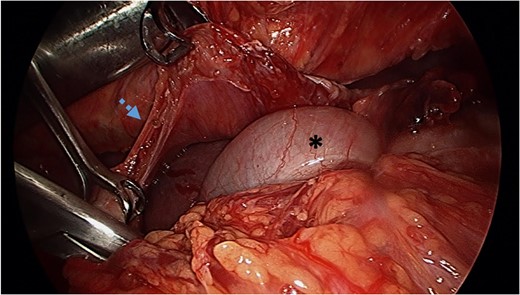

Video-assisted thoracoscopy (VAT) demonstrating a loop of transverse colon in the left hemithorax. Black asterisk (*) indicates a loop of transverse colon. Blue arrow indicates deflated left lung.